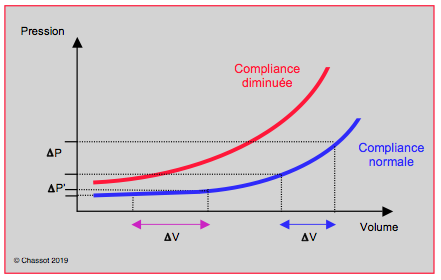

Visualisation des surfaces

La surface et le volume étant liés entre eux par une relation linéaire indépendante de la compliance, la visualisation directe des cavités cardiaques par l’échocardiographie est une voie privilégiée pour l'appréciation du degré de remplissage cardiaque. En vue transgastrique court-axe du VG, la variation de la surface endocavitaire télédiastolique gauche (StdVG mesurée au moment de l’onde R de l’ECG) a une sensibilité de 90% et une spécificité de 80% pour le diagnostic de l’hypovolémie (Vidéos) [15]. La StdVG décroît linéairement de 0.3 cm2 par 1% de déficit en volume circulant lors d’hémodilution [1]. Elle est un excellent indicateur de l’évolution du remplissage ventriculaire (r = 0.9) (Figure 27.2) [1,16]. Cette relation entre la surface et la volémie est maintenue en cas d'hypertrophie ventriculaire concentrique, de dysfonction diastolique ou d’insuffisance cardiaque, alors que, dans ce cas, la PVC et/ou la PAPO sont anormalement élevées pour le même degré de remplissage [19]. Les valeurs minimales du VG en court axe en dessous desquelles l’hypovolémie est probable sont : diamètre télédiastolique < 2.2 cm/m2, surface télédiastolique < 6 cm2/m2 [18]. En télésystole, il arrive que les muscles papillaires se touchent (kissing papillary muscles) tant le volume résiduel est faible ; bien que très sensible (sensibilité 99%), ce signe n’est pas spécifique (spécificité 30%) parce qu’il survient dès que la postcharge est basse, notamment lors de vasoplégie ou de contre-pulsion intra-aortique [8].

Figure 27.2 : Evaluation de la volémie à l'ETO par mesure de la surface télédiastolique du VG (StdVG en cm2) en court-axe transgastrique. A : la relation entre cette surface et le déficit en volume lors d'hémodilution aiguë est linéaire. En bleu: courbe chez des individus normaux; en rouge: courbe chez des insuffisants cardiaques gauches [1]. B : mesures de dimensions du VG: dessin de la surface (pointillé bleu) telle qu'elle est recommandée, n’incluant pas les muscles papillaires; flèche rouge: diamètre de la cavité du VG. C : rétrécissement télésystolique de la cavité en hypovolémie ou lors de vasoplégie.

La surface et le volume étant liés entre eux par une relation linéaire indépendante de la compliance, la visualisation directe des cavités cardiaques par l’échocardiographie est une voie privilégiée pour l'appréciation du degré de remplissage cardiaque. En vue transgastrique court-axe du VG, la variation de la surface endocavitaire télédiastolique gauche (StdVG mesurée au moment de l’onde R de l’ECG) a une sensibilité de 90% et une spécificité de 80% pour le diagnostic de l’hypovolémie (Vidéos) [15]. La StdVG décroît linéairement de 0.3 cm2 par 1% de déficit en volume circulant lors d’hémodilution [1]. Elle est un excellent indicateur de l’évolution du remplissage ventriculaire (r = 0.9) (Figure 27.2) [1,16]. Cette relation entre la surface et la volémie est maintenue en cas d'hypertrophie ventriculaire concentrique, de dysfonction diastolique ou d’insuffisance cardiaque, alors que, dans ce cas, la PVC et/ou la PAPO sont anormalement élevées pour le même degré de remplissage [19]. Les valeurs minimales du VG en court axe en dessous desquelles l’hypovolémie est probable sont : diamètre télédiastolique < 2.2 cm/m2, surface télédiastolique < 6 cm2/m2 [18]. En télésystole, il arrive que les muscles papillaires se touchent (kissing papillary muscles) tant le volume résiduel est faible ; bien que très sensible (sensibilité 99%), ce signe n’est pas spécifique (spécificité 30%) parce qu’il survient dès que la postcharge est basse, notamment lors de vasoplégie ou de contre-pulsion intra-aortique [8].

Figure 27.2 : Evaluation de la volémie à l'ETO par mesure de la surface télédiastolique du VG (StdVG en cm2) en court-axe transgastrique. A : la relation entre cette surface et le déficit en volume lors d'hémodilution aiguë est linéaire. En bleu: courbe chez des individus normaux; en rouge: courbe chez des insuffisants cardiaques gauches [1]. B : mesures de dimensions du VG: dessin de la surface (pointillé bleu) telle qu'elle est recommandée, n’incluant pas les muscles papillaires; flèche rouge: diamètre de la cavité du VG. C : rétrécissement télésystolique de la cavité en hypovolémie ou lors de vasoplégie.